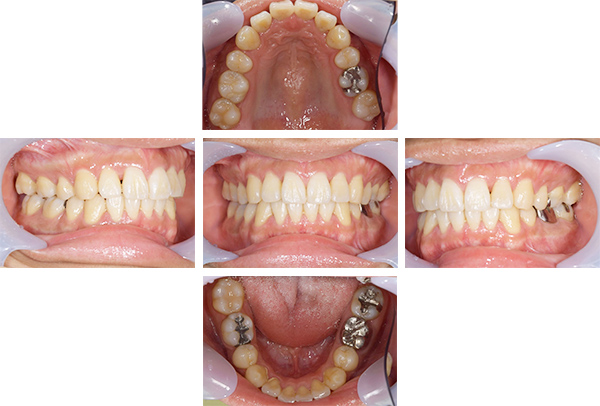

歯列矯正・インレー・クラウン症例

前歯が黒っぽいのが気になる、

悪いところは全部治したい

年齢 54代女性

主訴 歯をきれいにしたい

治療

期間

4年

費用 セラミックインレー 12本

660,000円

オールセラミックプレミアムクラウン 3本

495,000円

矯正 874,900円

計 2,029,900円(税込)

症例写真(治療前)

治療前:

八重歯が目立ちます。また銀歯もおおく、見た目が気になります。虫歯も散見できます。

治療中

担当医師所見

矯正装置をつけています。だんだん八重歯が動いてきているのがわかります。今回のケースでは、抜歯を行わずに矯正ができました。

症例写真(治療後)

治療後:

矯正治療と虫歯の治療すべて終わったときの写真になります。見た目も最初の頃とは全く違いますし、お口の中もすごく綺麗です。

方針

まずは虫歯の治療を行い、被せ物をする部分は仮歯をいれて矯正を行う。矯正終了後、仮歯の部分を最終的な被せ物に変えていく。また気になっていた銀歯もセラミックに変えて終了となった。

内容

セラミックインレー、オールセラミックプレミアム、矯正